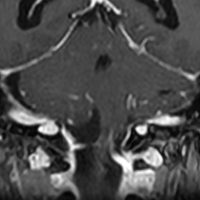

骨内髄膜腫 osseous meningioma

骨内増殖をする髄膜腫です。頭蓋骨腫瘍と間違えるようなものです。触った感じは骨腫ですが,CTでは,表面が毛羽立っていて,頭蓋冠に浸潤していることが特徴です。浅側頭動脈からの豊富な血流があります。

わずかですが頭蓋内にも腫瘍があり,硬膜が肥厚してガドリニウム増強されます。

頭蓋骨をかなり広範におかすので骨は捨てません。開頭して取り外した骨の厚くなっている部分と髄膜腫で軟らかくなっている部分を削除して,それから骨片をオートクレーブで短時間熱処理して,元あった所にもどします。下の画像は手術後1年半が経過したものですが,髄膜腫の再発はなく,熱処理骨弁は吸収されないで生着しています。